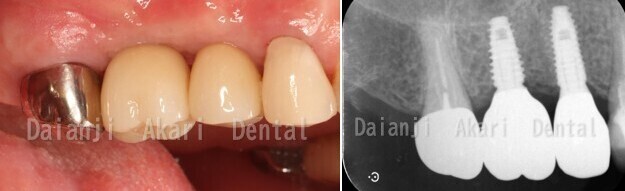

最終

インプラントの被せ物を入れて治療は終了しました。

その後はメンテナンスに移行します。

嚙み合わせ

治療内容:インプラント治療(骨造成術・遊離歯肉移植術含む)

治療期間:8か月

治療費用:47万円